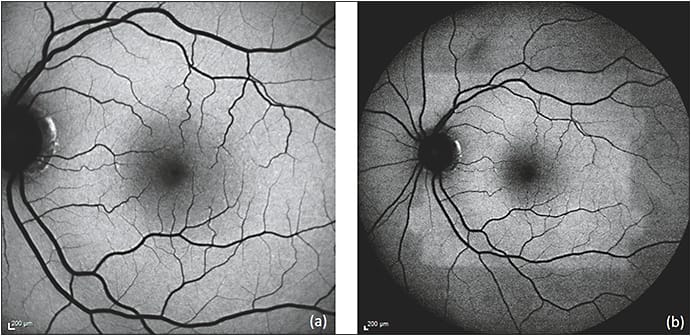

Rhodopsin, a visual pigment found in the rod photoreceptor outer segments, initially attenuates autofluorescence but undergoes photoisomerization with continued light exposure, resulting in the bleaching effect that leads to an increase of background autofluorescence of as much as 30% over time (Figure 1).15,16 The macular pigments lutein, zeaxanthin, and meso-zeaxanthin also filter blue light and protect the retina from photo-oxidative damage.17,18

Figure 1. Bleaching effect due to rhodopsin. Immediately after obtaining a 30 degree FAF (a), the 50 degree FAF (b) shows a discrete area of relative hyper-autofluorescence corresponding to an area of bleached photoreceptors resulting from the first image acquisition.

COURTESY OF BIOMED CENTRAL